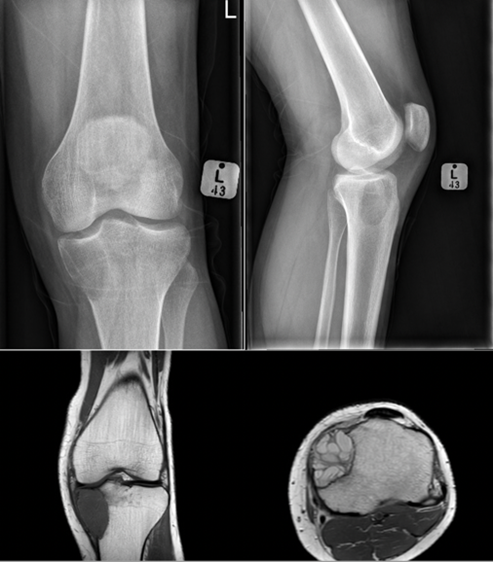

Giant cell tumour: A benign aggressive lesion of bone that has a soap bubble appearance on X-ray. Often found around the knee. It is usually metaphyseal and eccentric in the bone. It is named after its predominant cell type, which is of course the giant cell.

Osteosarcoma. There are many types of osteosarcoma but the most common is the classic intramedullary type which usually originates from the intramedullary cavity of the metaphyseal area of long bones. It is the most common type of bone sarcoma overall. It is most often found in teenagers and young adults. Any pathological fracture in a young person must be considered malignant until proven otherwise. The treatment of an osteosarcoma is classically neoadjuvant chemotherapy – surgery – adjuvant chemotherapy. The biopsy to diagnose bone sarcomas should be done by a sarcoma specialist to prevent difficulties with future surgery and spread of the tumour locally. The 5-year survival for patients with osteosarcoma is between 60% and 70%.

Endoprosthetic replacement. An example of a wide local resection of a patient who had an osteosarcoma of her proximal tibia. The initial X-rays show the pervasive lytic lesion of the proximal tibial diaphysis and metaphysis. The subsequent X-rays show an endoprosthetic replacement called a proximal tibial replacement. The knee has been replaced with a hinge-type knee replacement and the bone and tumour of the proximal tibia has been replaced by a modular metal prosthesis with a stem cemented into the distal femur and the proximal tibia.